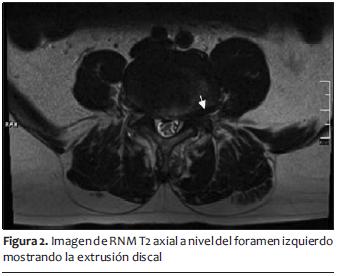

La punta de la aguja se ubicó en posición de hora 6:30 debajo del pedículo en enfoque anteroposterior, y en el tercio superior del foramen en visión lateral con una profundidad de 2/3 en el foramen.

Al inyectar 0,5 ml de contraste se observó la habitual imagen periradicular de L4 acompañada de una imagen intradiscal. Al inyectar otros 0,5 ml de contraste en tiempo real se observó el llenado del disco L4-L5 acompañado de dolor lumbar transitorio (figuras 3 y 4).